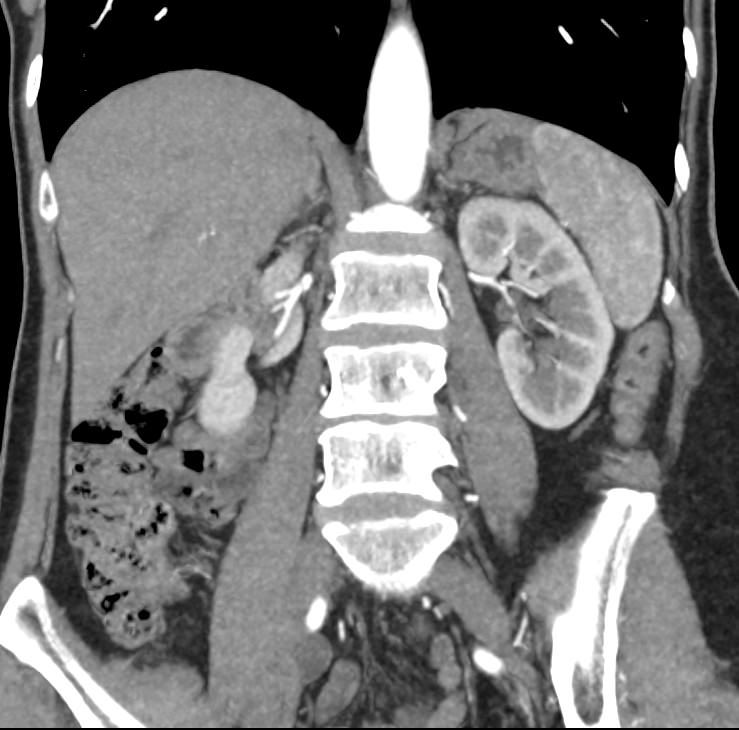

В компьютерном томографе излучатель рентгеновских лучей установлен в кольцевой части аппарата и, непрерывно вращаясь вокруг зоны исследования, производит послойное сканирование в различных плоскостях. В результате получаются снимки анатомической зоны в мельчайших подробностях, а после цифровой обработки полученных данных – точные трехмерные объемные модели исследуемой области. При этом изображения органов можно приблизить, повернуть в разные стороны, что значительно повышает точность диагностики различных заболеваний.

Для улучшения визуализации мягкотканных структур (внутренних органов, клетчаточных пространств, связок, мышц, сухожилий, кровеносных сосудов и лимфатических узлов) в ряде случаев проводится дополнительно контрастное усиление. Для этого пациенту внутривенно вводится йодсодержащий контрастный препарат, который активно поглощает рентгеновские лучи. Благодаря способности контраста накапливаться в патологических участках, они становятся хорошо видны на снимках КТ. Контрастное усиление позволяет оценить состояние сосудистой системы, выявить участки воспаления и опухолевые образования. С помощью контрастирования удается выявлять опухоли минимальных размеров, определить точные размеры и границы опухоли, степень ее воздействия на окружающие ткани.